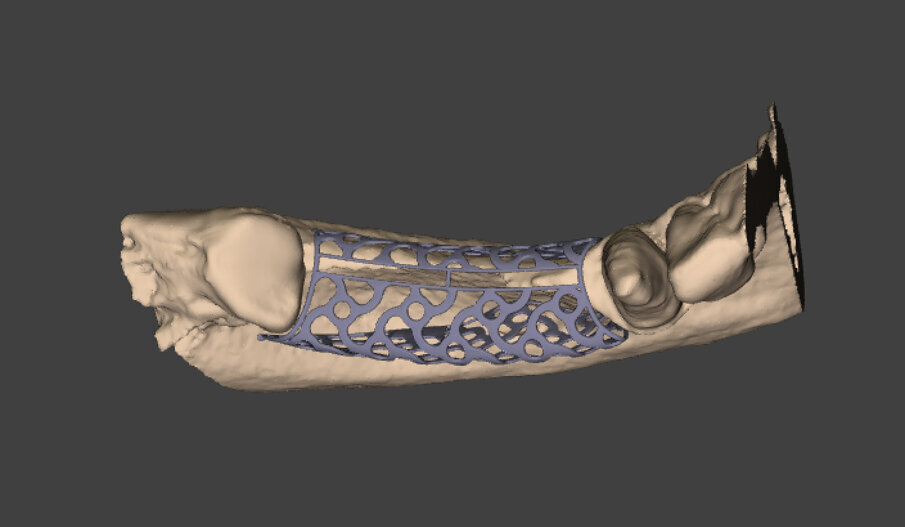

I file Dicom ottenuti sono stati inviati all’azienda produttrice delle griglie e da questi sono stati ricava - ti modelli tridimensionali in resina che riproducessero in modo fedele il deficit osseo; su questi modelli è stata costruita virtualmente e digitalmente la griglia che, dopo approvazione del clinico, è stata prodotta e inviata ai clinici (Figg. 2a, 2b). Le dimensioni mesio-distali della griglia erano di 21 mm e l’entità volumetri ca del deficit osseo di 1,24 cm 3 . Il piano di trattamento ha previsto, nel marzo 2018, un primo intervento di ricostruzione ossea del difetto mediante una griglia customizzata in titanio e, dopo 7 mesi (ottobre 2018), un secondo intervento ha permesso la rimozione della griglia con contestuale inserimento di 2 impianti endossei in posizione 4.4 e 4.6 per supportare un ponte fisso di 3 elementi protesici.

Figg. 2a, 2b_Modello digitale della situazione iniziale con il progetto definitivo della griglia in titanio customizzata Y-Xoss®.